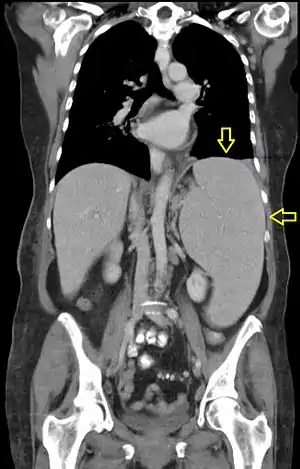

| CT scan in a patient with chronic lymphocytic leukemia, showing splenomegaly. Yellow arrows point at the spleen. | |